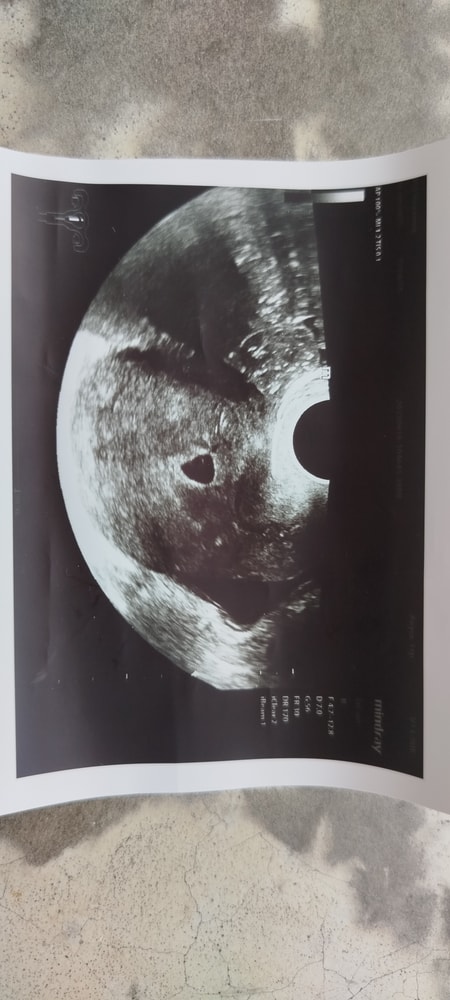

На 23дпп в платной клинике на узи увидели свд 11.5мм и ж.м.3.2мм

26дпп в больнице где я лежала на сохранении делают УЗИ и не видят ж.м. свд 14.6 Я была в полнейшей растерянности.В тот же день иду в платную клинику и там тоже не видят.

27дпп иду к специалисту что делала УЗИ на 23дпп и определила ж.м. и она видит свд 14мм ж.м. то

Сегодня 20дпп была на узи,легла на сохранение по рекомендации гинеколога просто что бы отдыхать.Увидели плодное яйцо свд 9мм и всё.Желточного мешочка пока не рассмотрели(((Что-то тревожно!Поделитесь у кого как было.